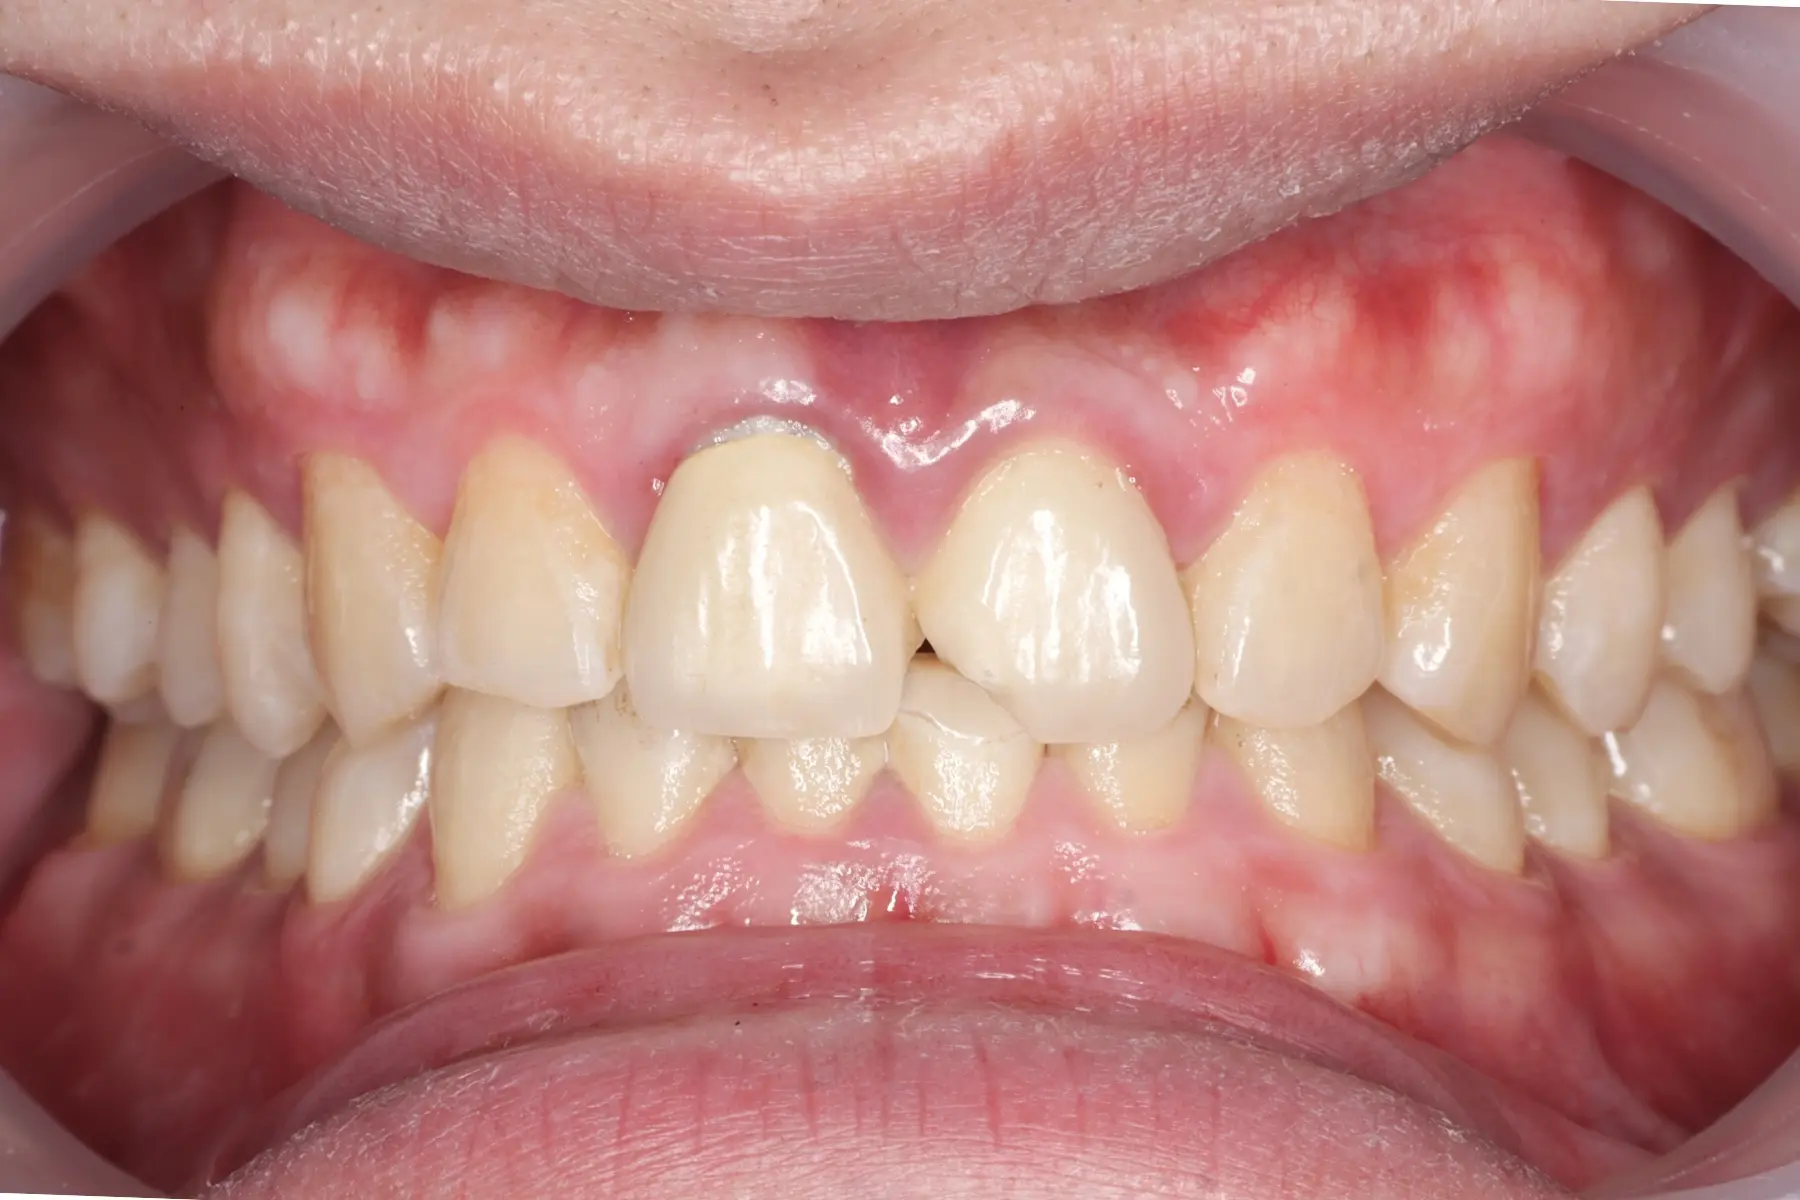

• 術前 42

術後 40

牙周治療

主治醫師

• 鍾國耀

治療時間

三次療程

主訴

牙齦紅腫出血、牙縫容易塞食物